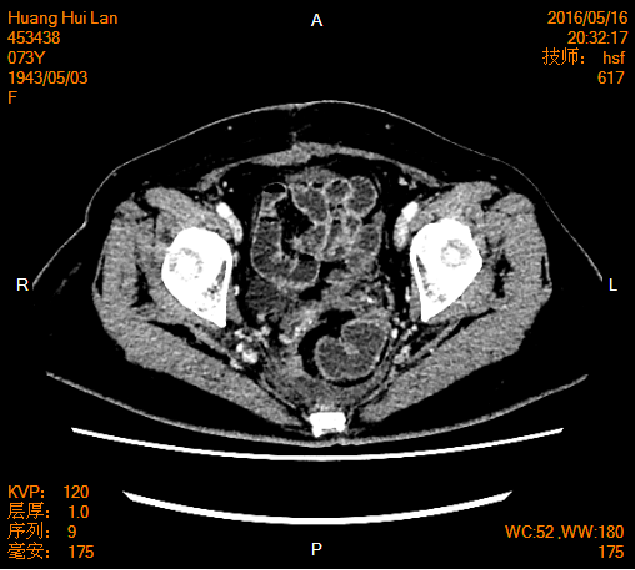

2016-04-13胸腹盆CT

左侧附件区肿块,代谢活跃,考虑卵巢囊腺癌;直肠壁增厚,代谢活跃,考虑直肠癌并周围淋巴结转移可能性大,建议肠镜检查;双肺多发结节,考虑转移瘤;腹腔积液

2016-05-17胸腹盆CT(术后基线)